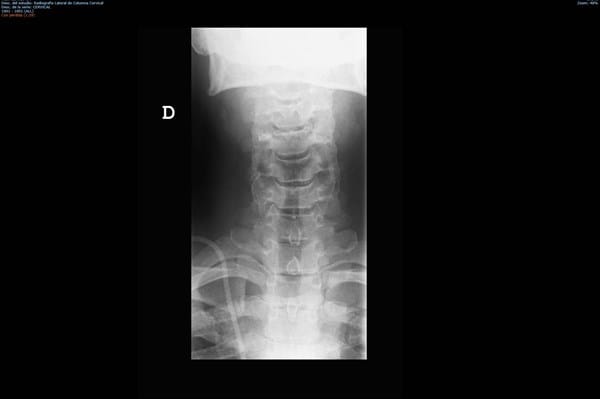

Aquí os coloco unas radiografías de cuello, me las han realizado por constracturas continuas y con dolor intenso.

Me han pedido unas radiografías en base a constracturas muy continuas y de larga duración desde hace como dos años, el asunto es que cada vez son más continuas. Tengo cita con mi médico de cabecera pero con todo este tema de covid van las cosas muy muy lentas.

¿Ustedes ven algo que justifique lo que me ocurre?